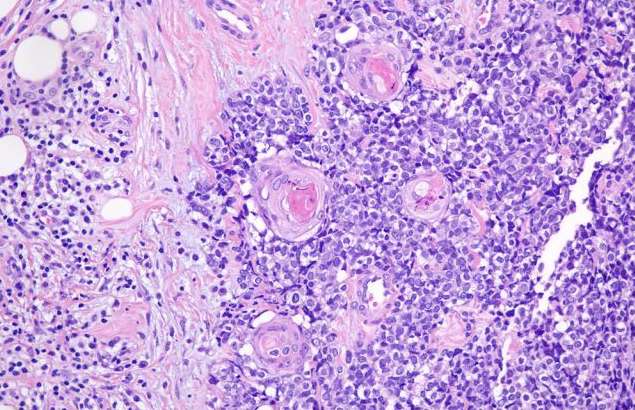

口腔恶性肿瘤是世界上常见的恶性肿瘤,在口腔癌中,约90%的患者为口腔鳞状细胞癌(oral squamous cell carcinoma,OSCC),严重威胁着人类健康。尽管近几年在OSCC的预防、诊断和治疗等方面取得了很大进展,但许多患者仍因转移和复发而死亡。上皮-间充质转化(epithelial-…